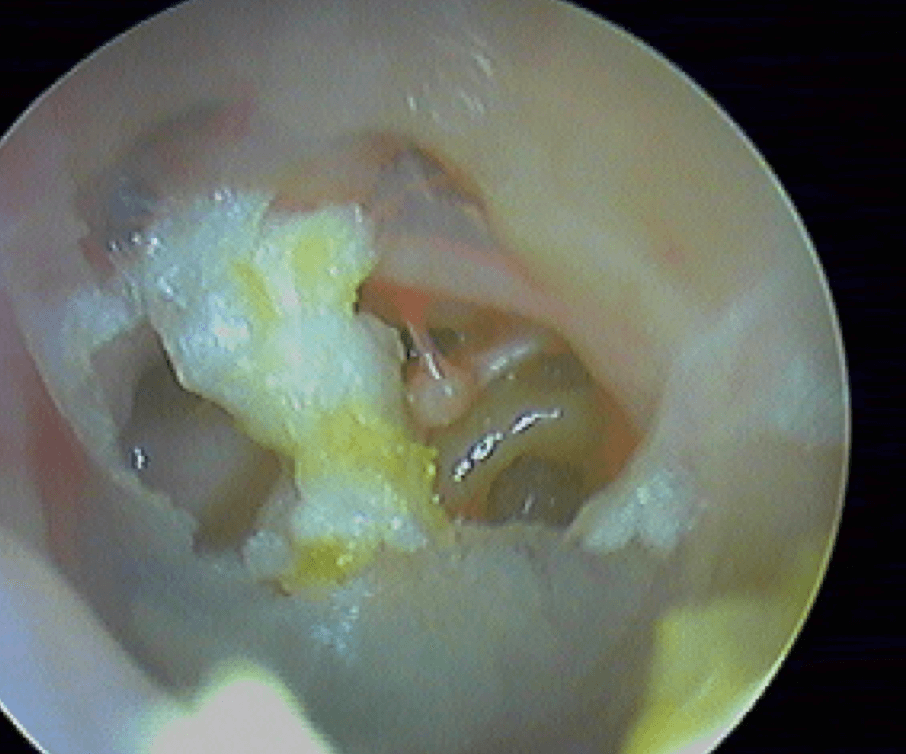

10/1 Cholestéatome acquis (secondaire)

Epithélium stratifié, kératinisé et squameux présent dans l’oreille moyenne, "croissance progressive de peau dans l’oreille", "skin in the wrong place": la peau malade du tympan va détruire tout sur son passage: le tympan lui-même, les osselets, le cadre osseux jusqu'à la méninge. Là il faut bien utiliser toutes ses connaissances sémiologiques d'otoscopie pour faire le diagnostic, qui est plus facile que l'otite atéléctasique, en raison de la présence de squames.

Cela touche adultes & enfants.

Le/la patient·e avait attendu quelques mois avant de revenir: le cholestéatome a englobé tout le malléus:

Se méfier du cérumen qui cache le cholestéatome: